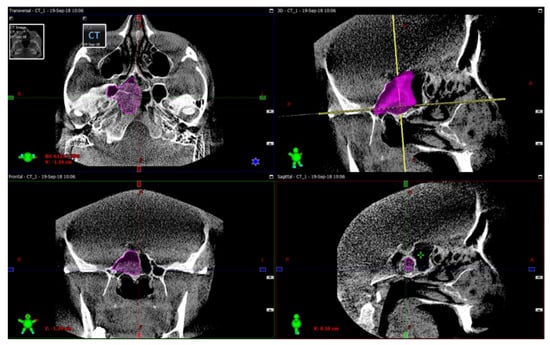

The procedure of the sphenoid sinus volume based on CT scanning followed by 3D reconstruction is illustrated in Figure 1. The corresponding intraoperative measurement procedures are illustrated in Figure 2, Figure 3 and Figure 4.

No significant differences in the sphenoid sinus volume were noticed between methylene blue and the preoperative CT scan in 39/40 cases (p < 10−6, Wilcoxon signed-rank nonparametric test). In one single case (denoted as patient 40 in Table 1), a significant discrepancy between the CT-based and the intraoperative volumes measurements of nearly 2 cm3 was observed. This unlikely discrepancy suggested the possible presence of remaining fungal masses in the sinus. The operation was continued to visualize the deep sections of the sphenoid, eventually leading to the confirmation of the above hypothesis. The remaining fungal masses were then successfully eliminated by repetitive irrigation. Another volume measurement confirmed that the pathological masses had been successfully removed, indicated by a small discrepancy of 0.3 cm3 (see Figure 5 for this single-case example).

Figure 1. Sphenoid sinus volume measurement procedure based on computed tomography (CT) scanning followed by 3D reconstruction. The opacification of the sphenoid sinus is marked in purple. The exemplified opacified sinus volume highlighted by violet in the figure equals 9.4 cm3. The green color denotes the scan area; the red color marks isocenter position; the blue color is horizontal axis; while the yellow line denotes the head anatomical axis.